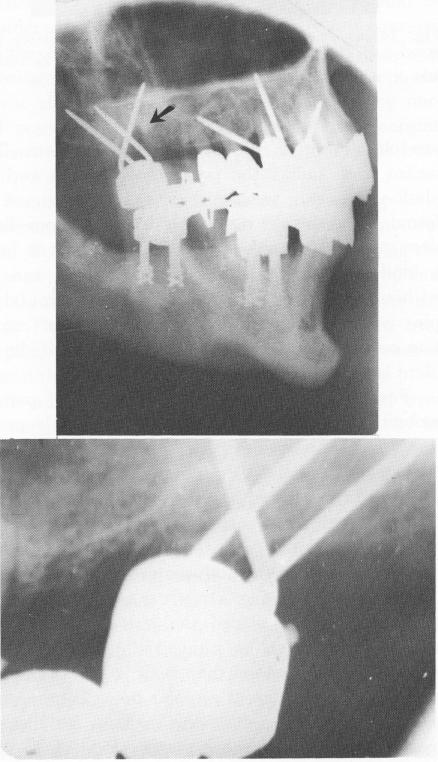

Fig. 14-22. A lateral plate roentgenogram and an intraoral periapical x-ray illustrate bone resorption in the areas where the pins are crossing over one another in the bone.

The deeper the triplant pins are set into bone and the more divergent they are, the greater the chance of success. The pins should diverge from one another, wherever possible, at least at a 45-degree angle. When they are too close to one another, bone resorption occurs (Fig. 14-21). Also, the pins should not cross one another in bone (Fig. 14-22).